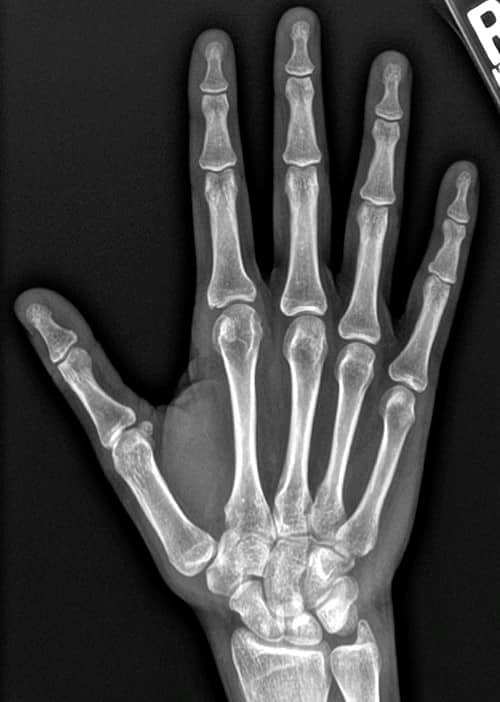

Oligoarthritis Juvenile Idiopathic Arthritis (JIA)